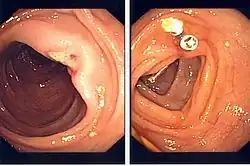

An ulcer seen after polypectomy (left) with a visible vessel suggesting recent bleeding is successfully closed with two endoclips (right)

Endoclips have also found an application in preventing bleeding when performing complicated endoscopic procedures. For example, prophylactic clipping of the base of a polyp has been found to be useful in preventing post-polypectomy bleeding, especially in high-risk patients or patients on anticoagulant medications.[19] In addition, clips can be used to close gastrointestinal perforations that may have been caused by complicated therapeutic endoscopy procedures, such as polypectomy, or by the endoscopic procedure itself.[20] Clips have also been used to secure the placement of endoscopic feeding tubes,[21] and to orient the bile duct to assist with endoscopic retrograde cholangiopancreatography, a procedure used to image to bile duct.[22]